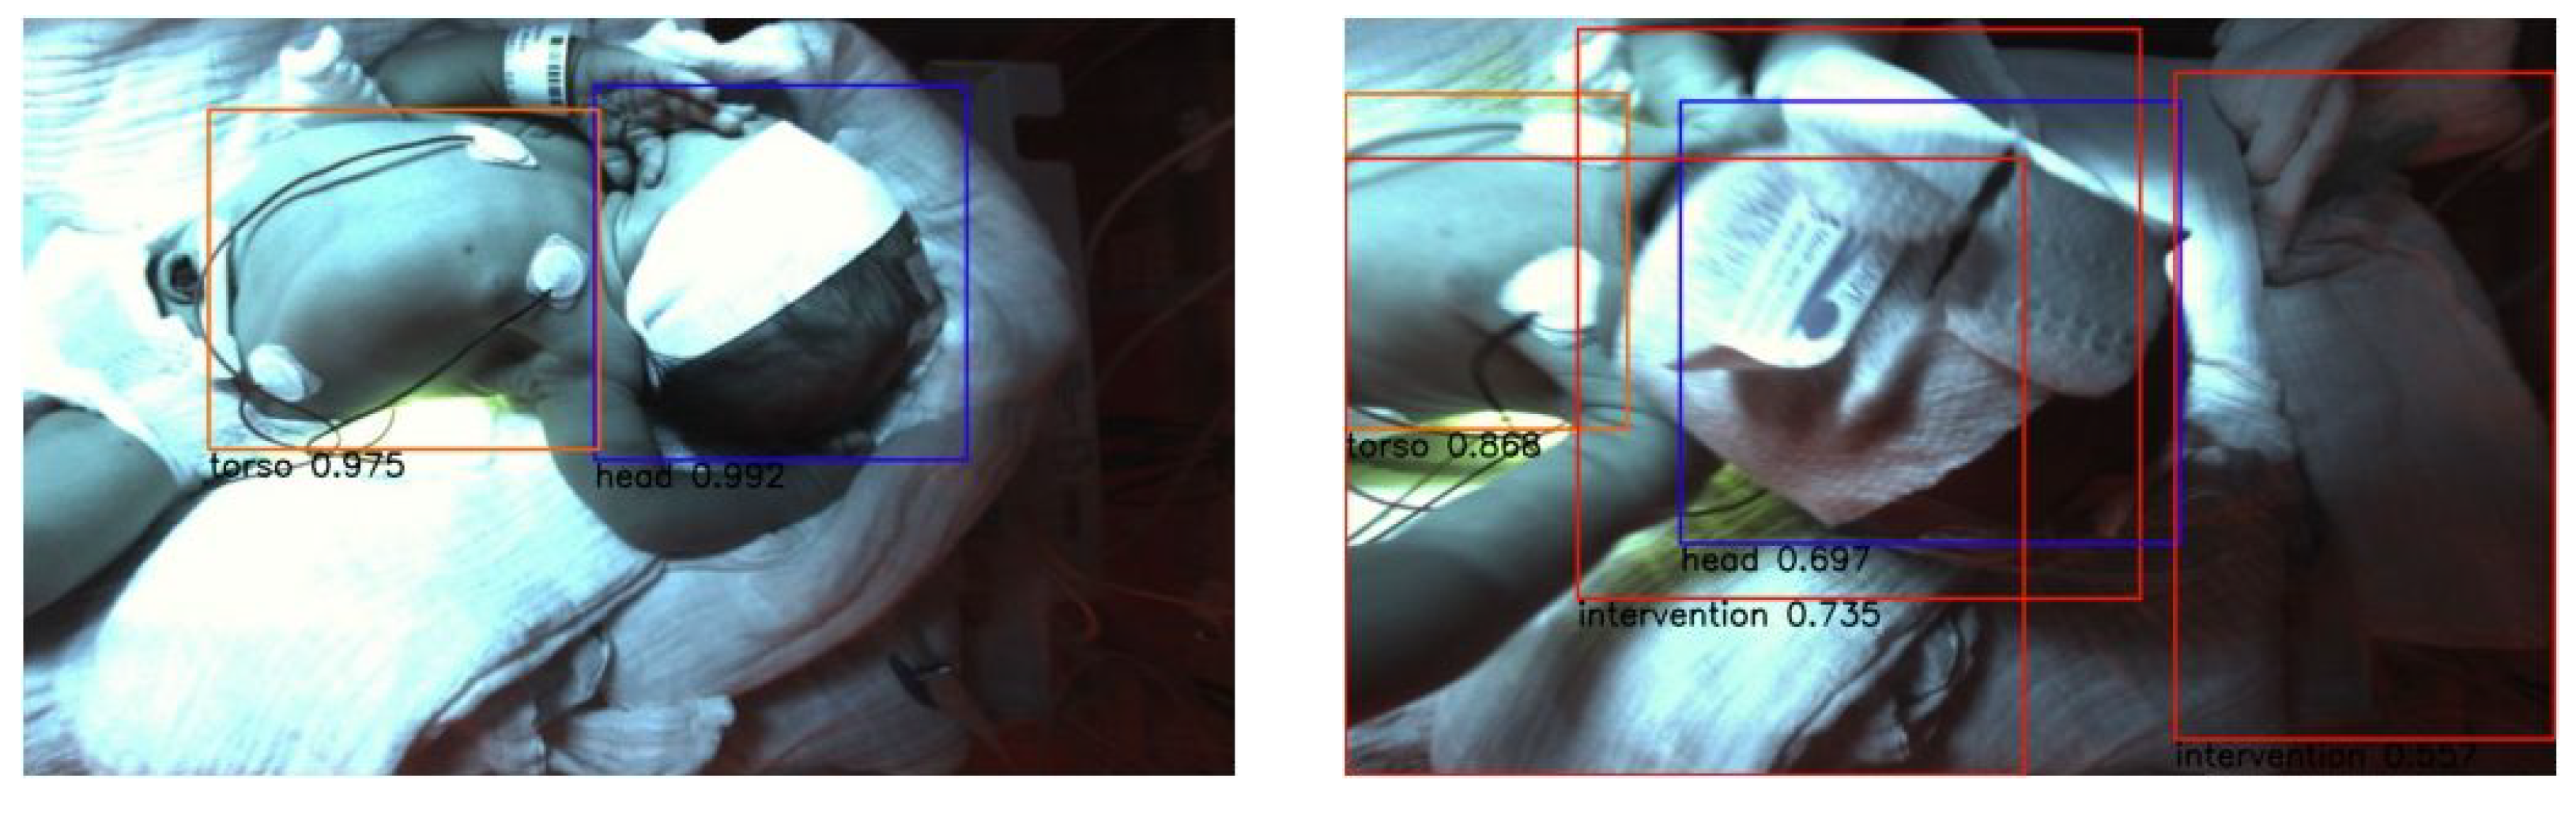

3.1. RGB Dataset

3.1.1. RetinaNet

3.1.2. YOLOv3

3.2. Thermal Dataset

3.2.1. RetinaNet

3.2.2. YOLOv3

3.3. Fusion Dataset

3.3.1. RetinaNet

3.3.2. YOLOv3